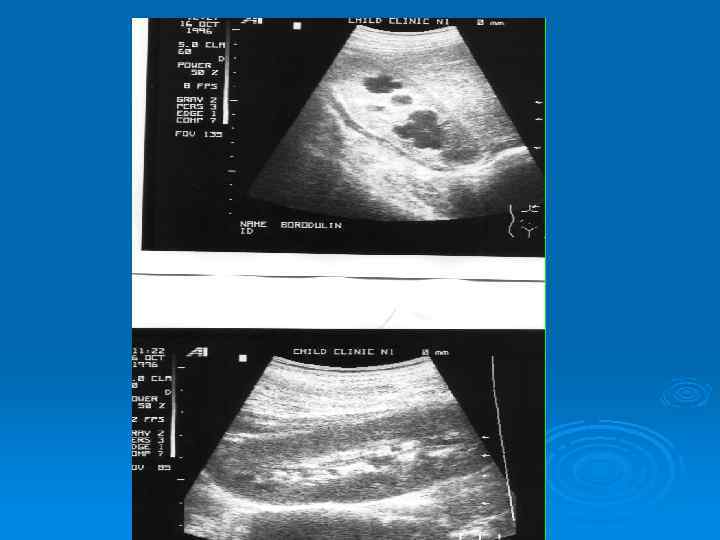

Микционная цистография

Микционная цистография По данным рентгенограммы – Двусторонний уретерогидронефроз, двусторонний мегауретер